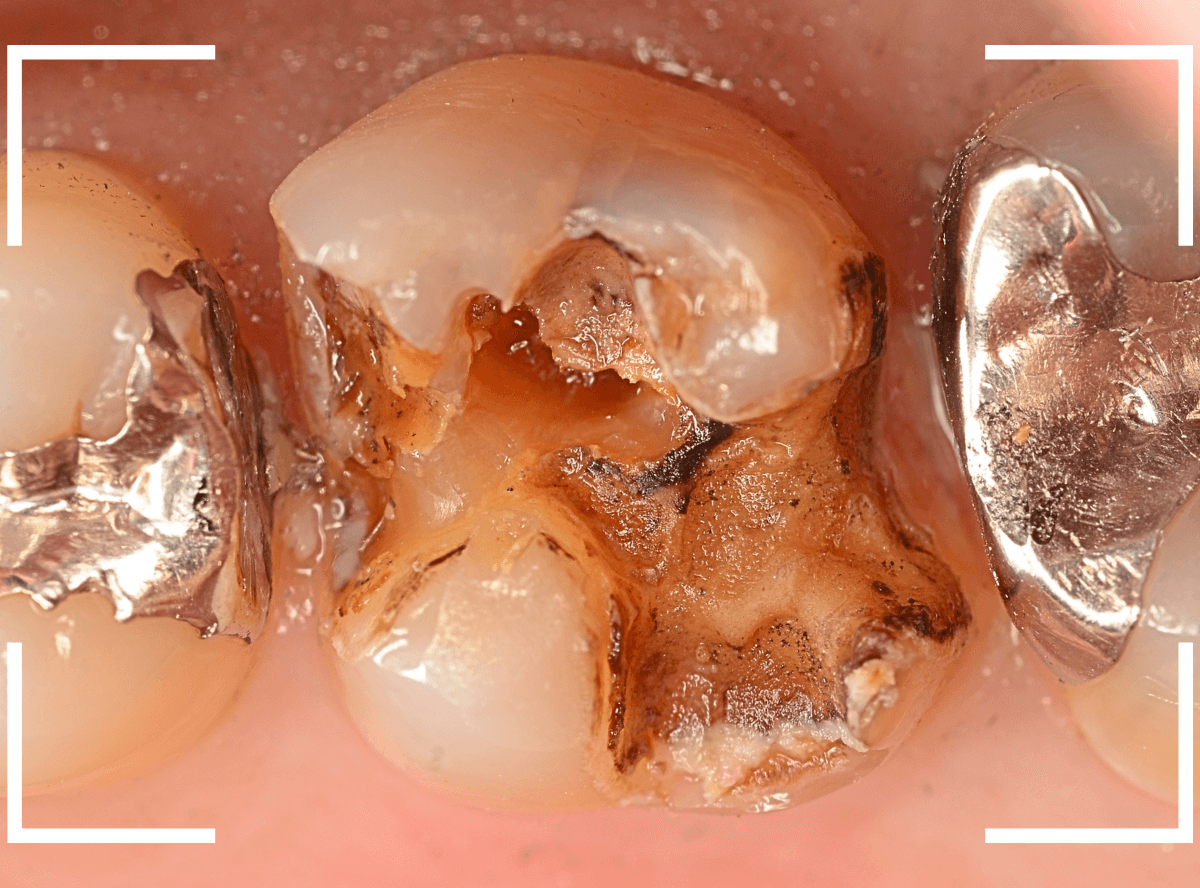

Case.16 金属の周りであちこちから虫歯

検診を希望された患者さんのケースです。

お口の中を拝見すると、上の奥歯の歯のすき間(隣接面)や、変色したレジンの中が怪しい感じです。

レントゲン写真で確認します。

青い線が神経で、赤い線が虫歯と思われる部分です。

奥から3歯が虫歯と思われますが、特に中央の歯の虫歯が深そうです。

まず、中央の歯の金属を除去します。

〇部分は前の治療時にしいたセメントです。この下に虫歯が広がっていると思われます。

セメントを除去したところです。

赤く染め出されているところが虫歯です。

神経に近くなっていますので、診療に虫歯を除去します。

側面のレジンや隣の歯との間の虫歯も慎重に除去します。

かなり広く虫歯が広がっています。

奥の歯の虫歯も全て除去しました。

3歯すべての虫歯を除去したところです。

しばらくお薬をつめて症状を経過観察した後、型どりをしてつめものを再製作する予定です。